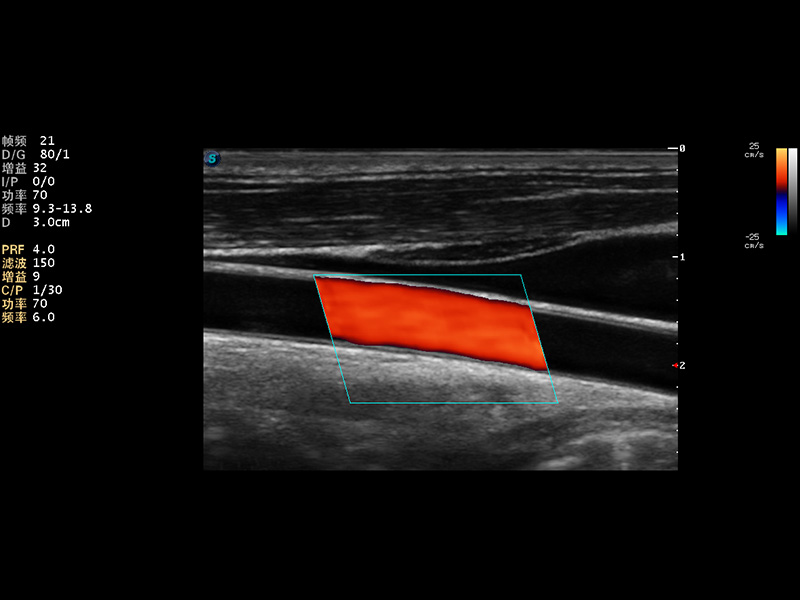

超声彩色多普勒诊断仪

2014年,开立医疗推出了全身应用型超声彩色多普勒诊断仪S22系列,在成像技术、人体工程学设计及工作流优化等方面,以卓越的临床图像、稳定的产品性能、齐全的应用功能充分满足几乎所有的科室的临床诊断需求。